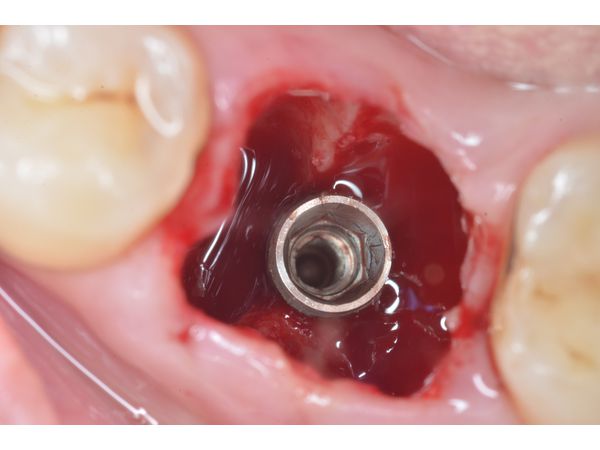

2. При помощи физиодиспенсера последовательно сформировано ложе под винтовой имплантат с использованием специальных фрез по модифицированному протоколу.

3. Установлен имплантат в позиции 4.6 зуба с первичной стабильностью 45 Н*см в костной ткани. Установка произведена в перегородку 4.6 зуба с необходимым заглублением по отношению к зениту будущей коронки.